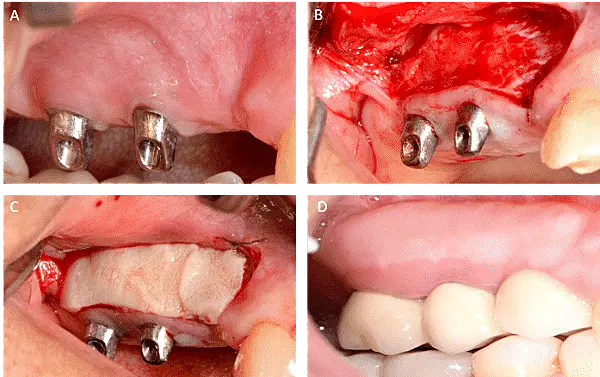

Caso clínico 1: aumento de tejido queratinizado mediante injerto gingival libre en implantes.

a: Ausencia de tejido queratinizado alrededor de implantes.

b: Colgajo a espesor parcial que ha sido desplazado apicalmente.

c: Injerto gingival epitelial sobre la zona de los dos implantes.

d: Se observa amplia cantidad de tejido queratinizado alrededor de los implantes a los 3 meses post operatorios.